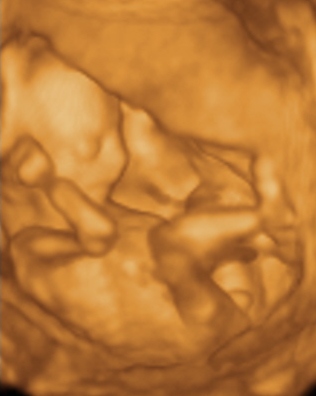

Princz- Babókád egyszerűen csodálatos, gratula!!

...Lányok tessék szépen példát venni!!